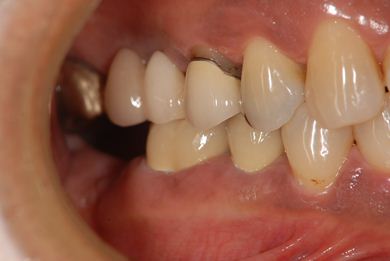

インプラントの症例写真 IMPLANT

インプラント治療+セラミック治療

| 治療内容 | インプラント2本、メタルボンドセラミッククラウン7本(メタルボンド用土台5本)、歯肉歯槽骨整形手術 | ||||||||||||||||||||||||||||||||